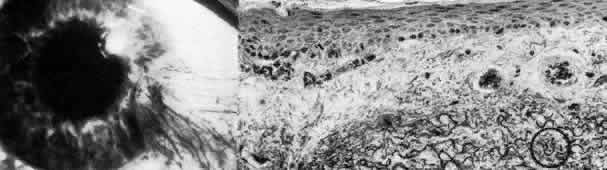

Fig. 15. Congenital hereditary endothelial dystrophy. Top left. Clinical photograph of eye of a 14-year-old male with severe form of the dystrophy shows diffuse ground-glass stromal opacification. Top middle. In a mildly affected 20-year-old female, the cornea has moderate diffuse haze and visual acuity is 20/200. Top right. On slit lamp biomicroscopy, diffuse edematous thickening of the corneal stroma is evident in same patient as top middle photograph. Middle right. Light microscopy of a case with uniformly thickened (approximately 35μm) Descemet's membrane (DM) covered posteriorly by extremely attenuated endothelial cells (arrowheads). S, posterior stroma; AC, anterior chamber (hematoxylin-eosin, × 600). Bottom left. Transmission electron micrograph of same case as middle right micrograph reveals anterior portion of Descemet's membrane (DM) to have normal thickness and banded structure. The markedly thickened (approximately 20 μm) posterior layer exhibits both 55 nm and 110 nm banding (circled) interspersed with homogeneous material. En, endothelial cell; AC, anterior chamber; S, posterior stroma (× 9200). Bottom right. At higher magnification, the abnormal posterior zone is seen to consist of multiple laminations of basement membrane-like material (*) and fine filaments. En, endothelial (× 42,000).

The degree of edematous corneal clouding varies from a mild haze to a milky, ground-glass opacification. Epithelial microbullae may be obvious, and stromal thickness may be increased threefold or more. Uniform thickening of Descemet's membrane is sometimes evident on clinical examination, but no guttata are apparent. Interstitial inflammation and secondary vascularization are absent. There are no definitely associated ocular or systemic abnormalities.

Histologic study175–181 reveals nonspecific anterior and stromal changes consistent with long-standing secondary edema: basal epithelial cell swelling, basement membrane thickening and disruptions, and irregularities of Bowman's layer with pannus formation. However, it may be significant that, in some cases, ultrastructural examination discloses greatly enlarged stromal collagen fibrils sometimes measuring as much as 60 nm in diameter. Descemet's membrane is uniform in a given specimen; it may display diffuse thinning of 3μm to massive thickening of 40 μm (normal thickness is 3 to 5 μm in neonates and 8 to 10 μm in adults). The anterior banded layer of Descemets membrane is always present and of relatively usual thickness; however, the posterior layer consists of multilaminar basement membrane-like material with fine filaments and of collagen fibrils with a 55- and 110-nm banded configuration. With the exception of the lack of guttata, these findings are similar to those in Fuchs' dystrophy and thus represent another example of posterior collagen layer formation by either primarily or secondarily abnormal endothelium.18,41,43,181, It is postulated that in cases with thin Descemet's membrane, complete endothelial loss occurred in utero such that only the fetal anterior portion of Descemet's membrane was secreted.180 In contrast, cases exhibiting thickened Descemet's membranes may be the product of dystrophic but persistent endothelium having secreted a hypertrophic posterior collagen layer.